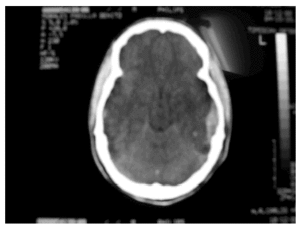

Hombre de 20 años que sufrió accidente de moto mientras circulaba con casco. En el lugar del accidente se objetivó un GSC 6. Se intubó y se trasladó a nuestro hospital. El estudio radiológico inicial mostraba las siguientes lesiones: fractura esfenoidal del arco cigomático, del seno maxilar y de la rama mandibular izquierda, fractura diafisaria de fémur izquierdo, fractura diafisaria de radio izquierdo. La TAC de cráneo no mostró lesiones intra ni extraaxiales (grado 5b de Gennarelli). Se colocó inicialmente un sensor intraparenquimatoso de PIC que mostró valores inferiores a 20 mmHg. Desde el tercer día se objetivaron, al menos, dos episodios diarios de duración superior a una hora, consistentes en hipertensión arterial, taquicardia, taquipnea, sudoración profusa, hipersalivación y contractura muscular generalizada. No guardaban una aparente relación con estímulos externos o internos y remitían espontáneamente o con bolos intravenosos adicionales de morfina, sobre una perfusión de 50 mg diarios de cloruro mórfico. Se utilizó también clonidina y labetalol intravenosos para intentar prevenir dichos episodios, sin resultado. A los 18 días de estancia se realizó una traqueotomía, lo que permitió la retirada de la ventilación mecánica. Al alta de la UCI, tras 25 días del accidente, mantenía un GSC de 8-9, sin déficit focal aparente, pero seguía presentando dichas crisis. A los 6 meses, el grado funcional había mejorado hasta un nivel 5 de la GOS, los episodios habían desaparecido y no requerían tratamiento.